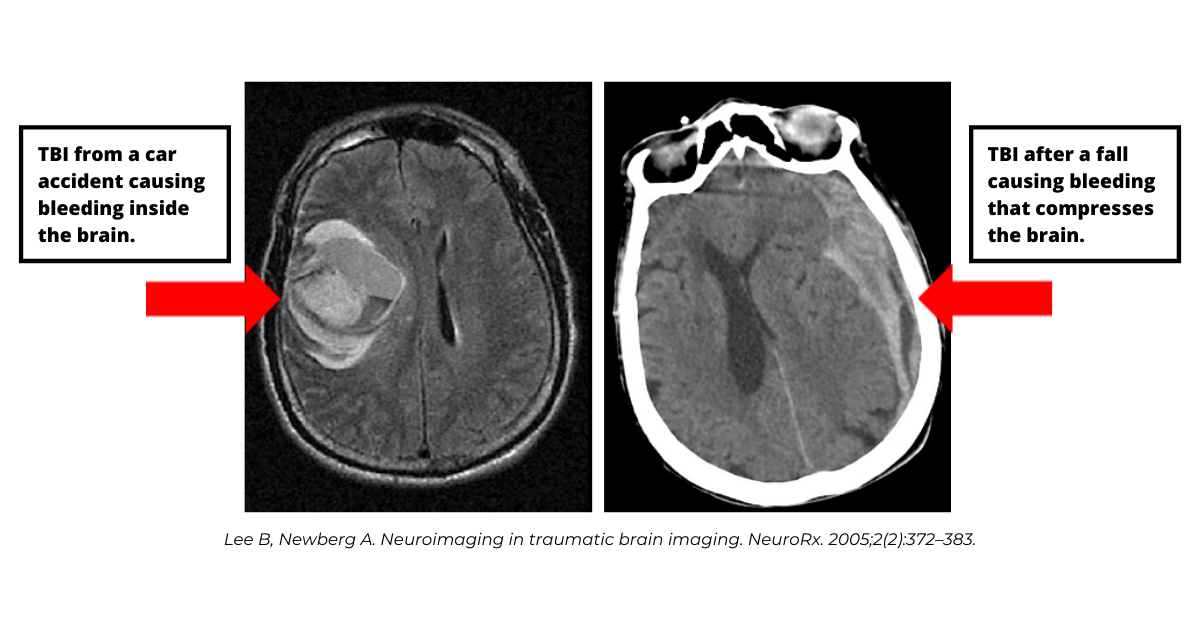

Depending on the type and severity of trauma a person experiences, TBI may cause bruising of the brain (brain contusion), bleeding inside the brain (intracerebral hemorrhage), bleeding between the coverings of the brain and the brain (subdural or subarachnoid hemorrhage), bleeding between the skull and coverings of the brain (epidural hematoma). Even if bleeding occurs outside of the brain it can have an impact on brain tissue by compressing the brain and disrupting normal brain anatomy and function. TBI can also cause mild to severe swelling of the brain (intracerebral edema).

Brain imaging with CT and when available brain MRI studies and electroencephalography (EEG) are routinely used to assess the degree of brain injury after a trauma. Blood work will also be done to identify any toxic, infectious or endogenous cause that may have facilitated the development of the head trauma and identify any blood loss.